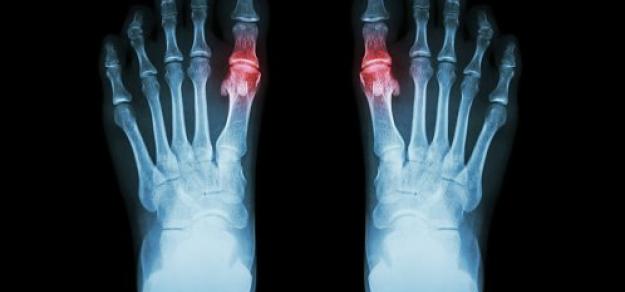

En pacientes con gota y sin enfermedad coronaria, el uso prolongado de alopurinol protege contra el primer síndrome coronario agudo (SCA) en comparación con los no usuarios. Por el contrario, los iniciadores del alopurinol, que posiblemente tenían más inflamación sistémica, tenían un mayor riesgo de SCA por primera vez en comparación con los usuarios a largo plazo. BMJ Open, 27 de febrero de 2025